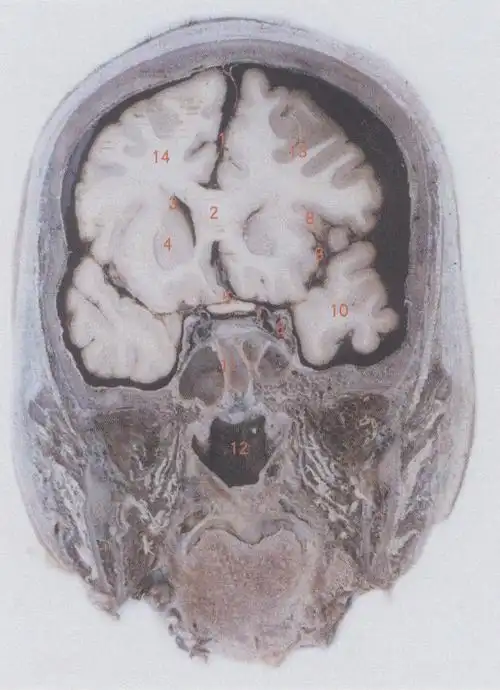

脑部断层解剖 大脑镰 额叶 中央前回 中央沟 中央后回 中央旁

1大脑镰cerebralfalx2胼胝体corpuscallosurn3侧脑室lateralventricle